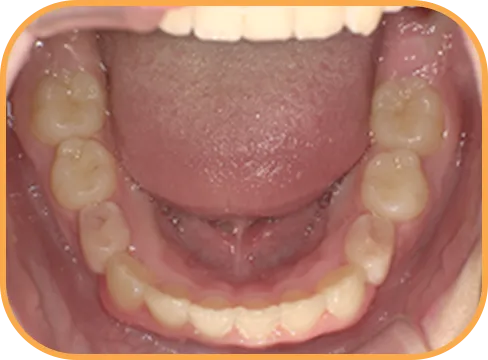

• After

• 正 面

治療後正面からの歯の様子

• 下 顎

治療後下顎からの歯の様子

主 訴

前歯ガタガタ、前歯が大きい

治療内容

インビザライン・ファースト

治療期間

7か月

治療費(税別)

450,000円+診断料5,000円

リスク・副作用

• 親知らずの影響や加齢などによって、凸凹が生じる可能性があります。

• 治療の初期段階では痛みや不快感が生じやすくなりますが、1週間前後で慣れます。

• 顎の成長発育によって、噛み合わせや歯並びが変化する可能性があります。

• 状況により当初予定した治療計画を変更する可能性があります。